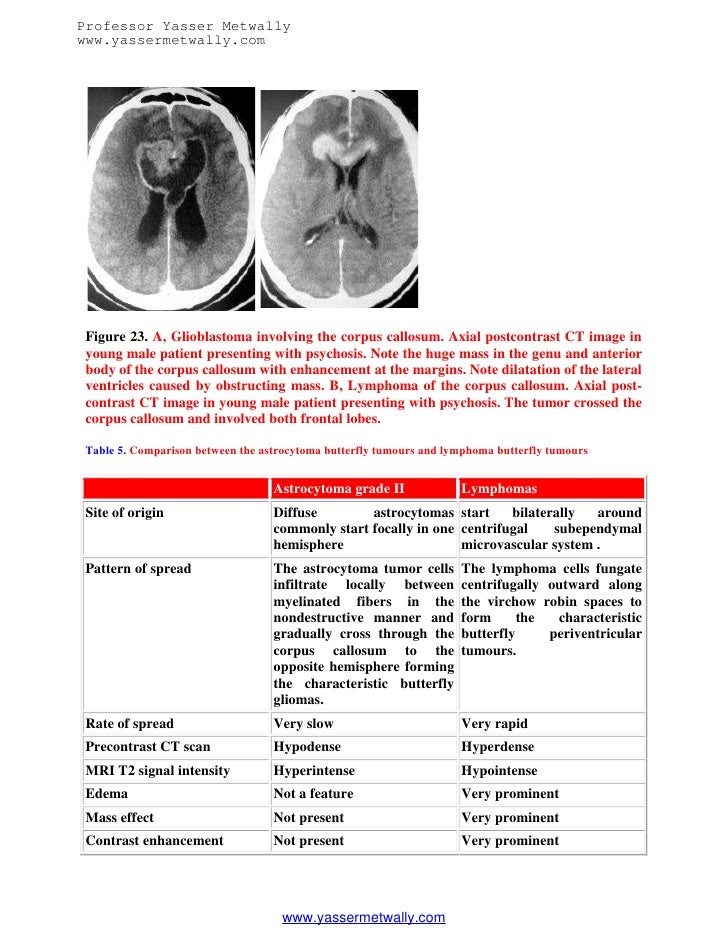

View Glioblastoma Butterfly Tumor US. These tumors start in astrocytes. Typical appearances of a butterfly glioma, with little possible differential.

Learn vocabulary, terms and more with flashcards, games and other study glioblastoma with oligodendroglial features, gliocsarcoma, giant cell glioblatoma, pediatric. 6,383 likes · 19 talking about this. Other white matter commissures are also occasionally involved.

Overview of common imaging features found with glioblastoma, characteristic pathologic findings, and relevant clinical features. Although understanding of glioblastoma has improved in recent. The grade of the tumor glioblastomas are what's known as primary brain tumors. Glioblastoma tumors make their own blood supply, which helps them grow.